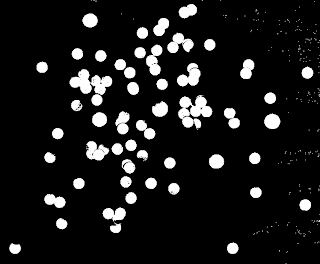

We can use the opening and closing operations to look for cancer cells (larger cells) in a pool of normal cells. Let's pretend that this image is an image of normal cells

|

| normal cells |

and this an image of normal cells with larger cancer cells

First, I cut the image into 256x256 subimages and binarized the images. Choosing carefully the threshold to separate the background from the cells. By looking at the histogram of the grayed image, we were able to determine the threshold (~0.84).

Binarized subimages.

The opening operator is then applied to separate closely placed cells. The strel used is a 5x5-pixel circle with the center at the topmost left 1-valued pixel.

Opened subimages.